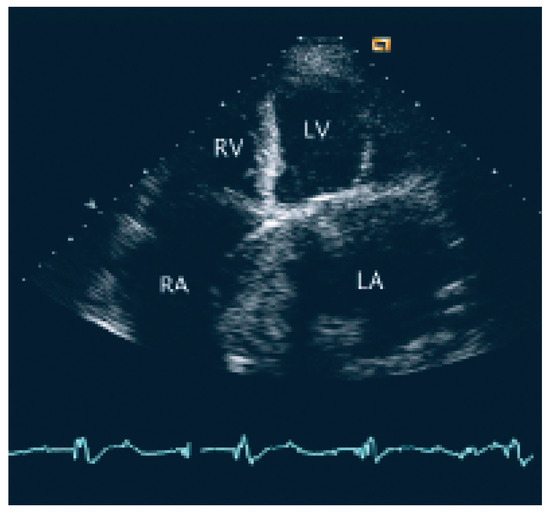

Coronary and Peripheral Thromboembolism from a Giant Left Atrium

by Marcello Di Valentino, Andrea Menafoglio, Ludwig von Segesser, Jeanne-Marie Segatto and Augusto Gallino

Cardiovasc. Med. 2006, 9(1), 28; https://doi.org/10.4414/cvm.2006.01144 - 27 Jan 2006

We report the case of a patient with a history of mitral valve replacement and a giant left atrium with acute transmural anterior myocardial infarction and concomitant acute occlusion of the right superficial femoral artery [...] Full article